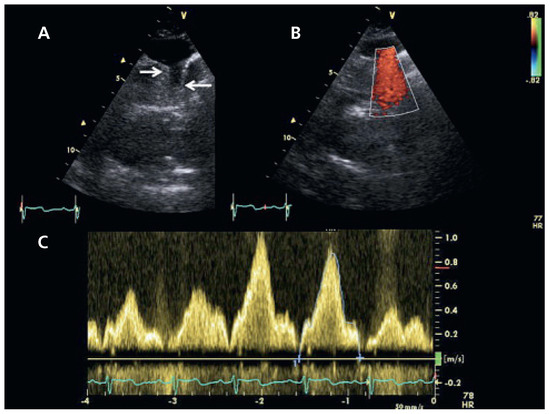

Une échocardiographie transthoracique est donc demandée à la recherche d’une étiologie cardiaque à la dyspnée. Cet examen montre une fonction systolique biventriculaire conservée, une hypertrophie importante et une dilatation modérée du ventricule droit (Figure 1). La pression systolique dans l’artère pulmonaire, calculée au moyen de la vitesse maximale de régurgitation tricuspidienne est estimée à 65 mm Hg. La recherche soigneuse d’un shunt G/D ne met pas en évidence de défect du septum interauriculaire.

Figure 1. (A) Vue en 4 cavités en diastole. Dilatation des cavités droites. (B) Vue sous-costale en diastole: hypertrophie de la paroi libre du ventricule droit (flèches). (C) Flux de régurgitation tricuspidien permettant d’évaluer la pression systolique pulmonaire à 65 mm Hg en estimant la pression de l’oreillette droite à 10 mm Hg.